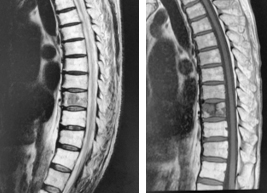

(1)胸椎に肺癌の転移性腫瘍を認めます。脳転移などもあったため、根治的手術は困難でした。

(2)経皮的椎弓根スクリューを用いた特殊な方法で、脊椎を安定化しています。

術後、麻痺の改善と疼痛の緩和を認めました。

腰の第4番目、5 番目の椎体が感染し、進行性の骨破壊と後弯変形を認めます。経皮的椎弓根スクリューを用いた特殊な方法で、脊椎を安定化しています。

(左)術前の進行性の骨破壊が見られましたが、(右)術後1年では良好な骨癒合が得られています。